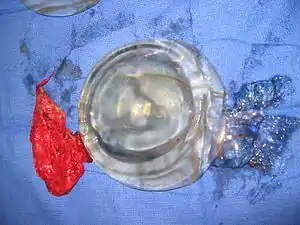

Implant rupture

Because a breast implant is a Class III medical device of limited product-life, the principal rupture-rate factors are its age and design; nonetheless, a breast implant device can retain its mechanical integrity for decades in a woman's body.[43] When a saline breast implant ruptures, leaks, and empties, it quickly deflates, and thus can be readily explanted (surgically removed). In some cases, saline implant rupture can result in an infection due to bacteria or mold that had been within the implant, though this is uncommon.[44] The follow-up report, Natrelle Saline-filled Breast Implants: a Prospective 10-year Study (2009) indicated rupture-deflation rates of 3–5 per cent at 3-years post-implantation, and 7–10 per cent rupture-deflation rates at 10-years post-implantation.[45] In a study of his 4761 augmentation mammaplasty patients, Eisenberg reported that overfilling saline breast implants 10-13% significantly reduced the rupture-deflation rate to 1.83% at 8-years post-implantation.[46]

When a silicone breast implant ruptures it usually does not deflate, yet the filler gel does leak from it, which can migrate to the implant pocket; therefore, an intracapsular rupture (in-capsule leak) can become an extracapsular rupture (out-of-capsule leak), and each occurrence is resolved by explantation. Although the leaked silicone filler-gel can migrate from the chest tissues to elsewhere in the woman's body, most clinical complications are limited to the breast and armpit areas, usually manifested as granulomas (inflammatory nodules) and axillary lymphadenopathy (enlarged lymph glands in the armpit area).[47][48][49]